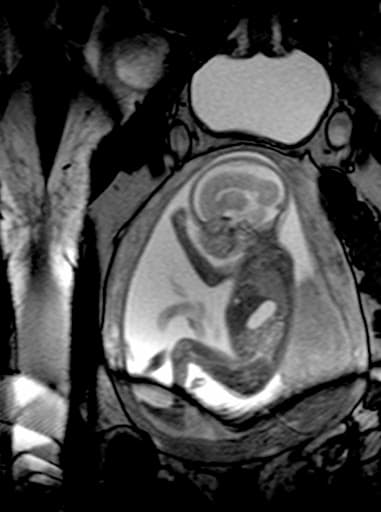

Examine the health of your baby in the womb in detail with Fetal MRI. Choose our medical imaging center for reliable MRI imaging and radiology services!